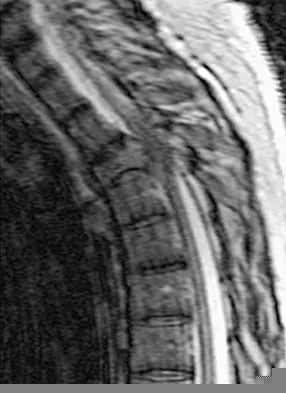

A 19-year-old man has had back pain with activity, especially running in soccer and baseball, for the past 4 months. He denies any history of trauma. Examination reveals no motor weakness or sensory changes in the lower extremities. Range of motion shows increased pain with extension and mild limitation with flexion. A sitting straight leg raising test is limited at approximately 60 degrees bilaterally by back and buttocks pain. Plain radiographs are normal. MRI scans are shown in Figures 13a through 13e. What is the most likely diagnosis?

Explanation